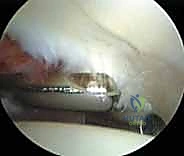

3. الجولة التشخيصية داخل المفصل (Diagnostic Arthroscopy)

بمجرد دخول الكاميرا، يتم عرض صورة مكبرة وعالية الدقة (4K) لداخل المفصل على شاشة كبيرة. يقوم الدكتور هطيف بفحص جميع الهياكل بدقة متناهية: الغضروف المفصلي، الشفا الحقي، الرباط المدور، والبحث عن أي التهابات أو أجسام سائبة. يتم استخدام سائل ملحي معقم لضخ المفصل، مما يوسع المساحة ويغسل الدم لضمان رؤية واضحة تماماً.

4. الإجراء العلاجي (The Intervention)

بناءً على ما تم تشخيصه، يقوم الجراح بتنفيذ الإجراءات التالية باستخدام أدوات آلية دقيقة (Shavers, Burrs, Radiofrequency probes):

* إصلاح الشفا الحقي (Labral Repair): إذا كان الشفا ممزقاً ولكن نسيجه لا يزال جيداً، يتم إعادة تثبيته في حافة الحُق باستخدام خطاطيف صغيرة جداً (Suture Anchors) تزرع في العظم وتمرر خيوطاً قوية لربط النسيج الممزق.

* تنظيف الشفا (Labral Debridement): إذا كان النسيج الممزق تالفاً جداً ولا يمكن خياطته، يتم تشذيبه وإزالة الأجزاء المتهتكة لتخفيف الألم ومن